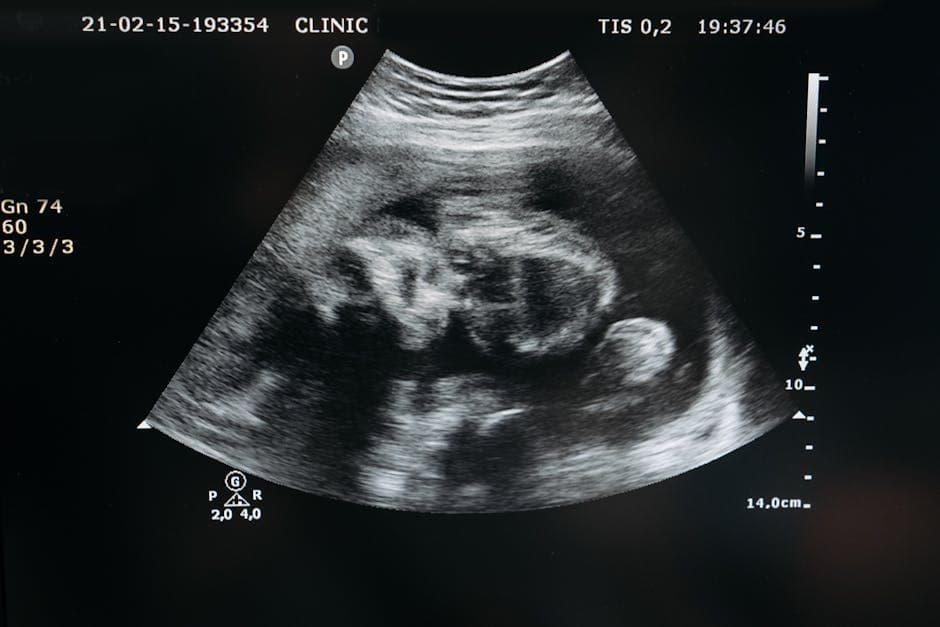

Ultrasound machines use sound waves to create images. When sound waves hit dense tissue (like bone), they bounce back strongly and appear bright white on the screen. This brightness is called "echogenicity."

Soft tissues, like the fetal intestines (bowel), usually appear gray. An echogenic bowel simply means that a section of the baby's intestines is showing up on the monitor as bright white,roughly as bright as the surrounding bone.

"It’s crucial to remember that this is an ultrasound finding,a trick of the light and sound waves,not a structural birth defect. The baby's bowel is fully formed and physically intact."